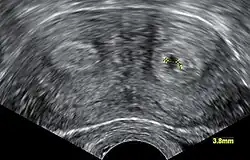

Diagnosis of bicornuate uterus typically involves imaging of the uterus with 2D or 3D ultrasound, hysterosalpingography, or magnetic resonance imaging (MRI). On imaging, a bicornuate uterus can be distinguished from a septate uterus by the angle between the cornua (intercornual angle): less than 75 degrees in a septate uterus, and greater than 105 degrees in a bicornuate uterus. Measuring the depth of the cleft between the cornua (fundal cleft) may also assist in diagnosis; a cleft of over 1 centimetre (0.39 in) is indicative of bicornuate uterus.[2]